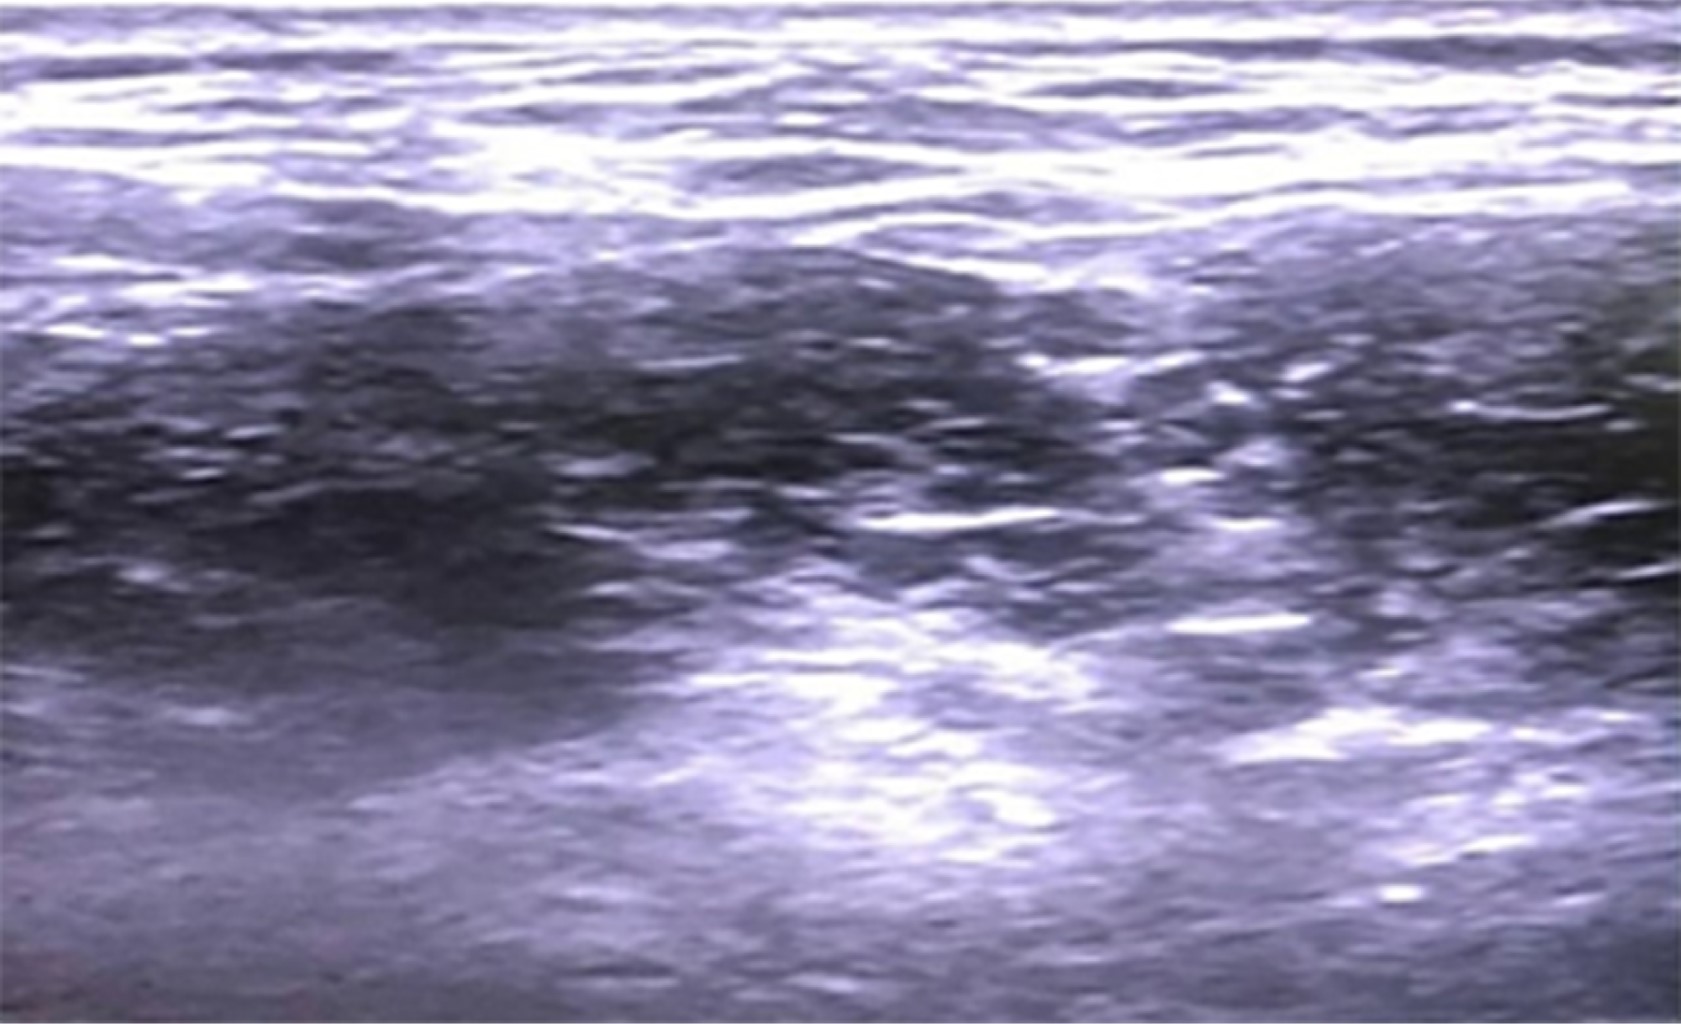

Una vez asegurada la vía aérea, con técnica estéril y bajo visión ecográfica, ultrasonido GE Logic P6 PRO, transductor lineal 12 MHz, se coloca bloqueo del plexo braquial de abordaje interescalénico con técnica en plano aguja ecogénica 21 G y se administra ropivacaína 0.5% 15 mL más dexmedetomidina 50 μg perineural (Figura 3).

Figura 3